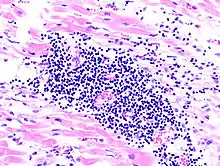

Mikro: Interstitielles lymphozytäres Infiltrat (kleine blaue Zellen), kaum Nekrosen.

![]() Virale Myokarditis bei Patient mit plötzlichem kongestiven Herzversagen, Autopsiepräparat, H&E. |

![]() idem. |